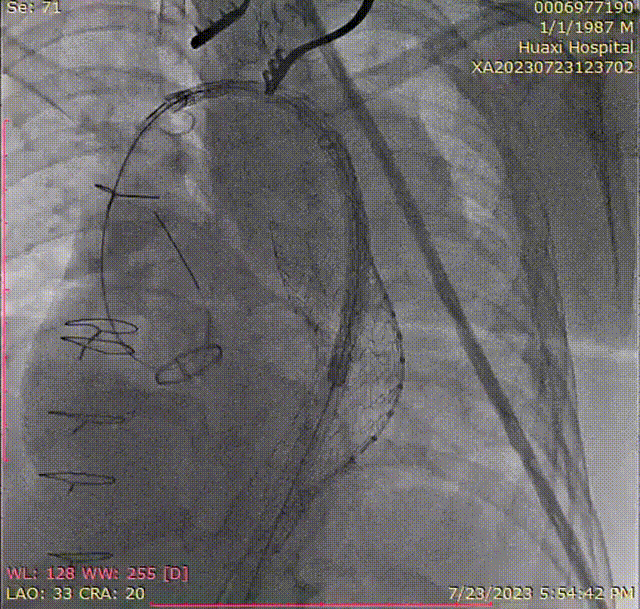

2. 经右侧股动脉穿刺入路,确认导丝在真腔,行胸主动脉段造影。

gore医疗怎么样「胸有乾坤」可调可控 精准出击——四川大学华西医院肖正华教授团队:CADS治疗B型主动脉夹层病例分享_https://www.jmylbn.com_新闻资讯_第19张

术中入路造影

gore医疗怎么样「胸有乾坤」可调可控 精准出击——四川大学华西医院肖正华教授团队:CADS治疗B型主动脉夹层病例分享_https://www.jmylbn.com_新闻资讯_第20张

确认真腔

3. 交换lunderquist超硬导丝,置入DSF2265导引鞘,沿导引鞘先置入GORE® TAG® 胸主动脉覆膜支架系统 TGU313115,造影确认支架位置并释放。

gore医疗怎么样「胸有乾坤」可调可控 精准出击——四川大学华西医院肖正华教授团队:CADS治疗B型主动脉夹层病例分享_https://www.jmylbn.com_新闻资讯_第21张

释放远端CTAG